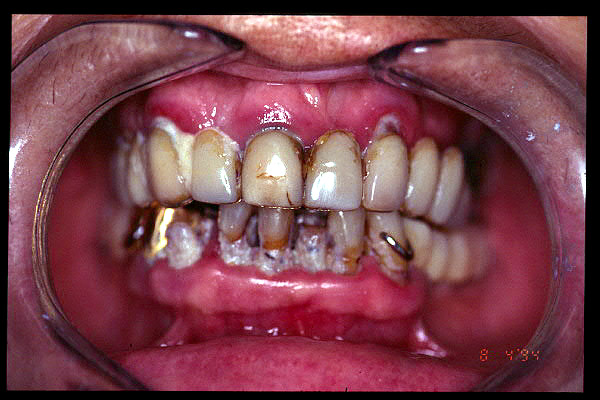

CM Caries, patología periodontal, desgaste.